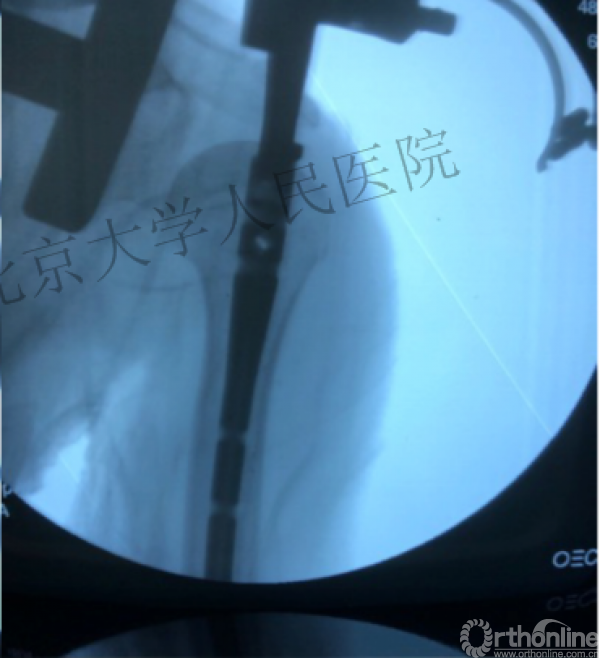

术中片

进钉更完美——我们的帮助

透视肱骨头正位、侧位确定进针点